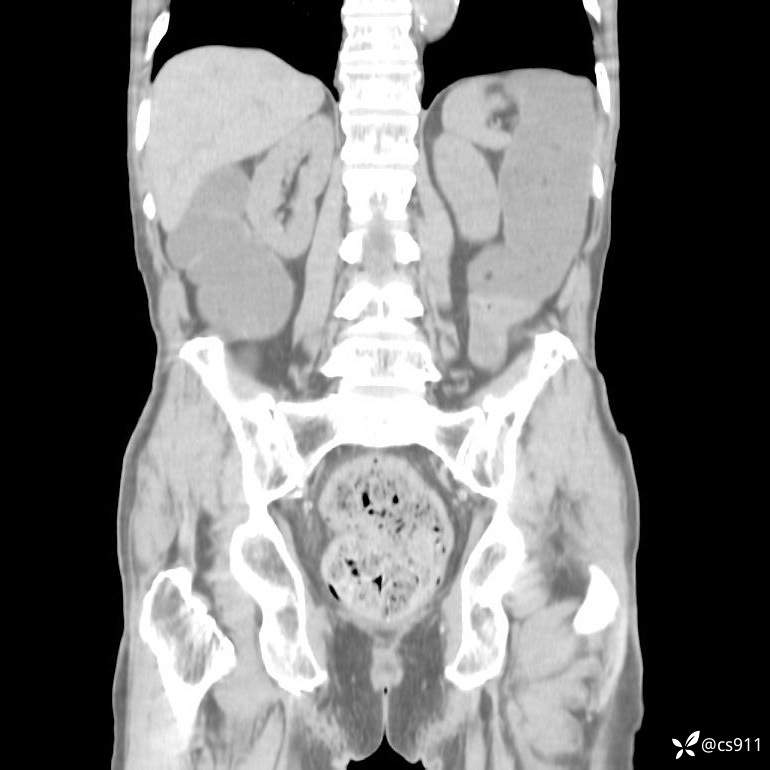

急腹症之急诊CT,原因?答案公布

男,77岁,腹痛、腹胀伴恶心呕吐1天。呕吐胃内容物,非喷射性呕吐,有咖啡色样胃内容物,诉有胃穿孔病史。查体:全腹平,下腹部压痛,全腹无反跳痛,叩诊呈浊音,移动性浊音阴性,肠鸣音减弱,1-2次/分。肛检:直肠未扪及明显肿物,可触及大量粪块。

血淀粉酶(AMY) HH 1859 U/L 35-135

癌胚抗原(CEA) H 27.44 ng/ml 0-5